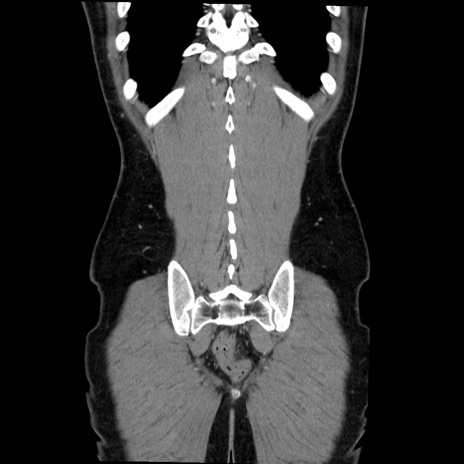

症例36(冠状断像)

【症例】20歳代 男性

【主訴】心窩部痛

【現病歴】今朝より上腹部痛あり。一旦軽快していたが再度出現したため救急要請。昨日夕に白身の魚を含む刺身を食べた。

【身体所見】BP 136/89mmHg、HR 74/min、BT 37.0℃、腹部:膨満、軟、心窩部に圧痛あり。反跳痛なし、筋性防御なし、腸雑音やや亢進あり。

【データ】WBC 17700、CRP 0.48